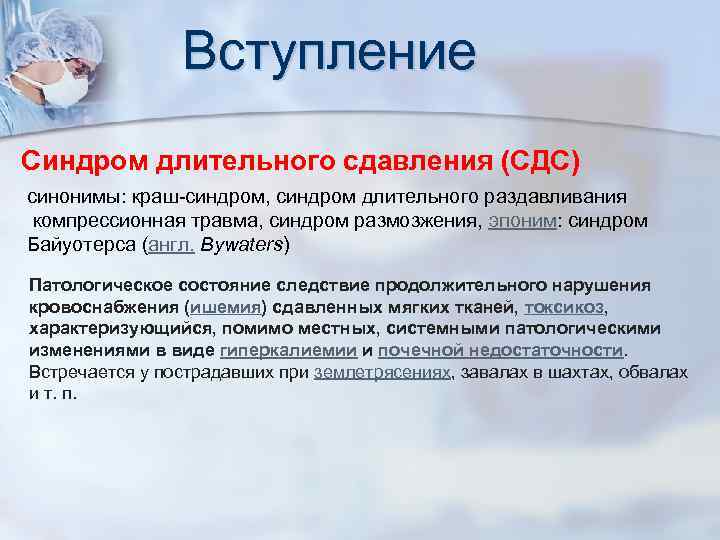

Классификация синдрома длительного раздавливания: основные категории и признаки